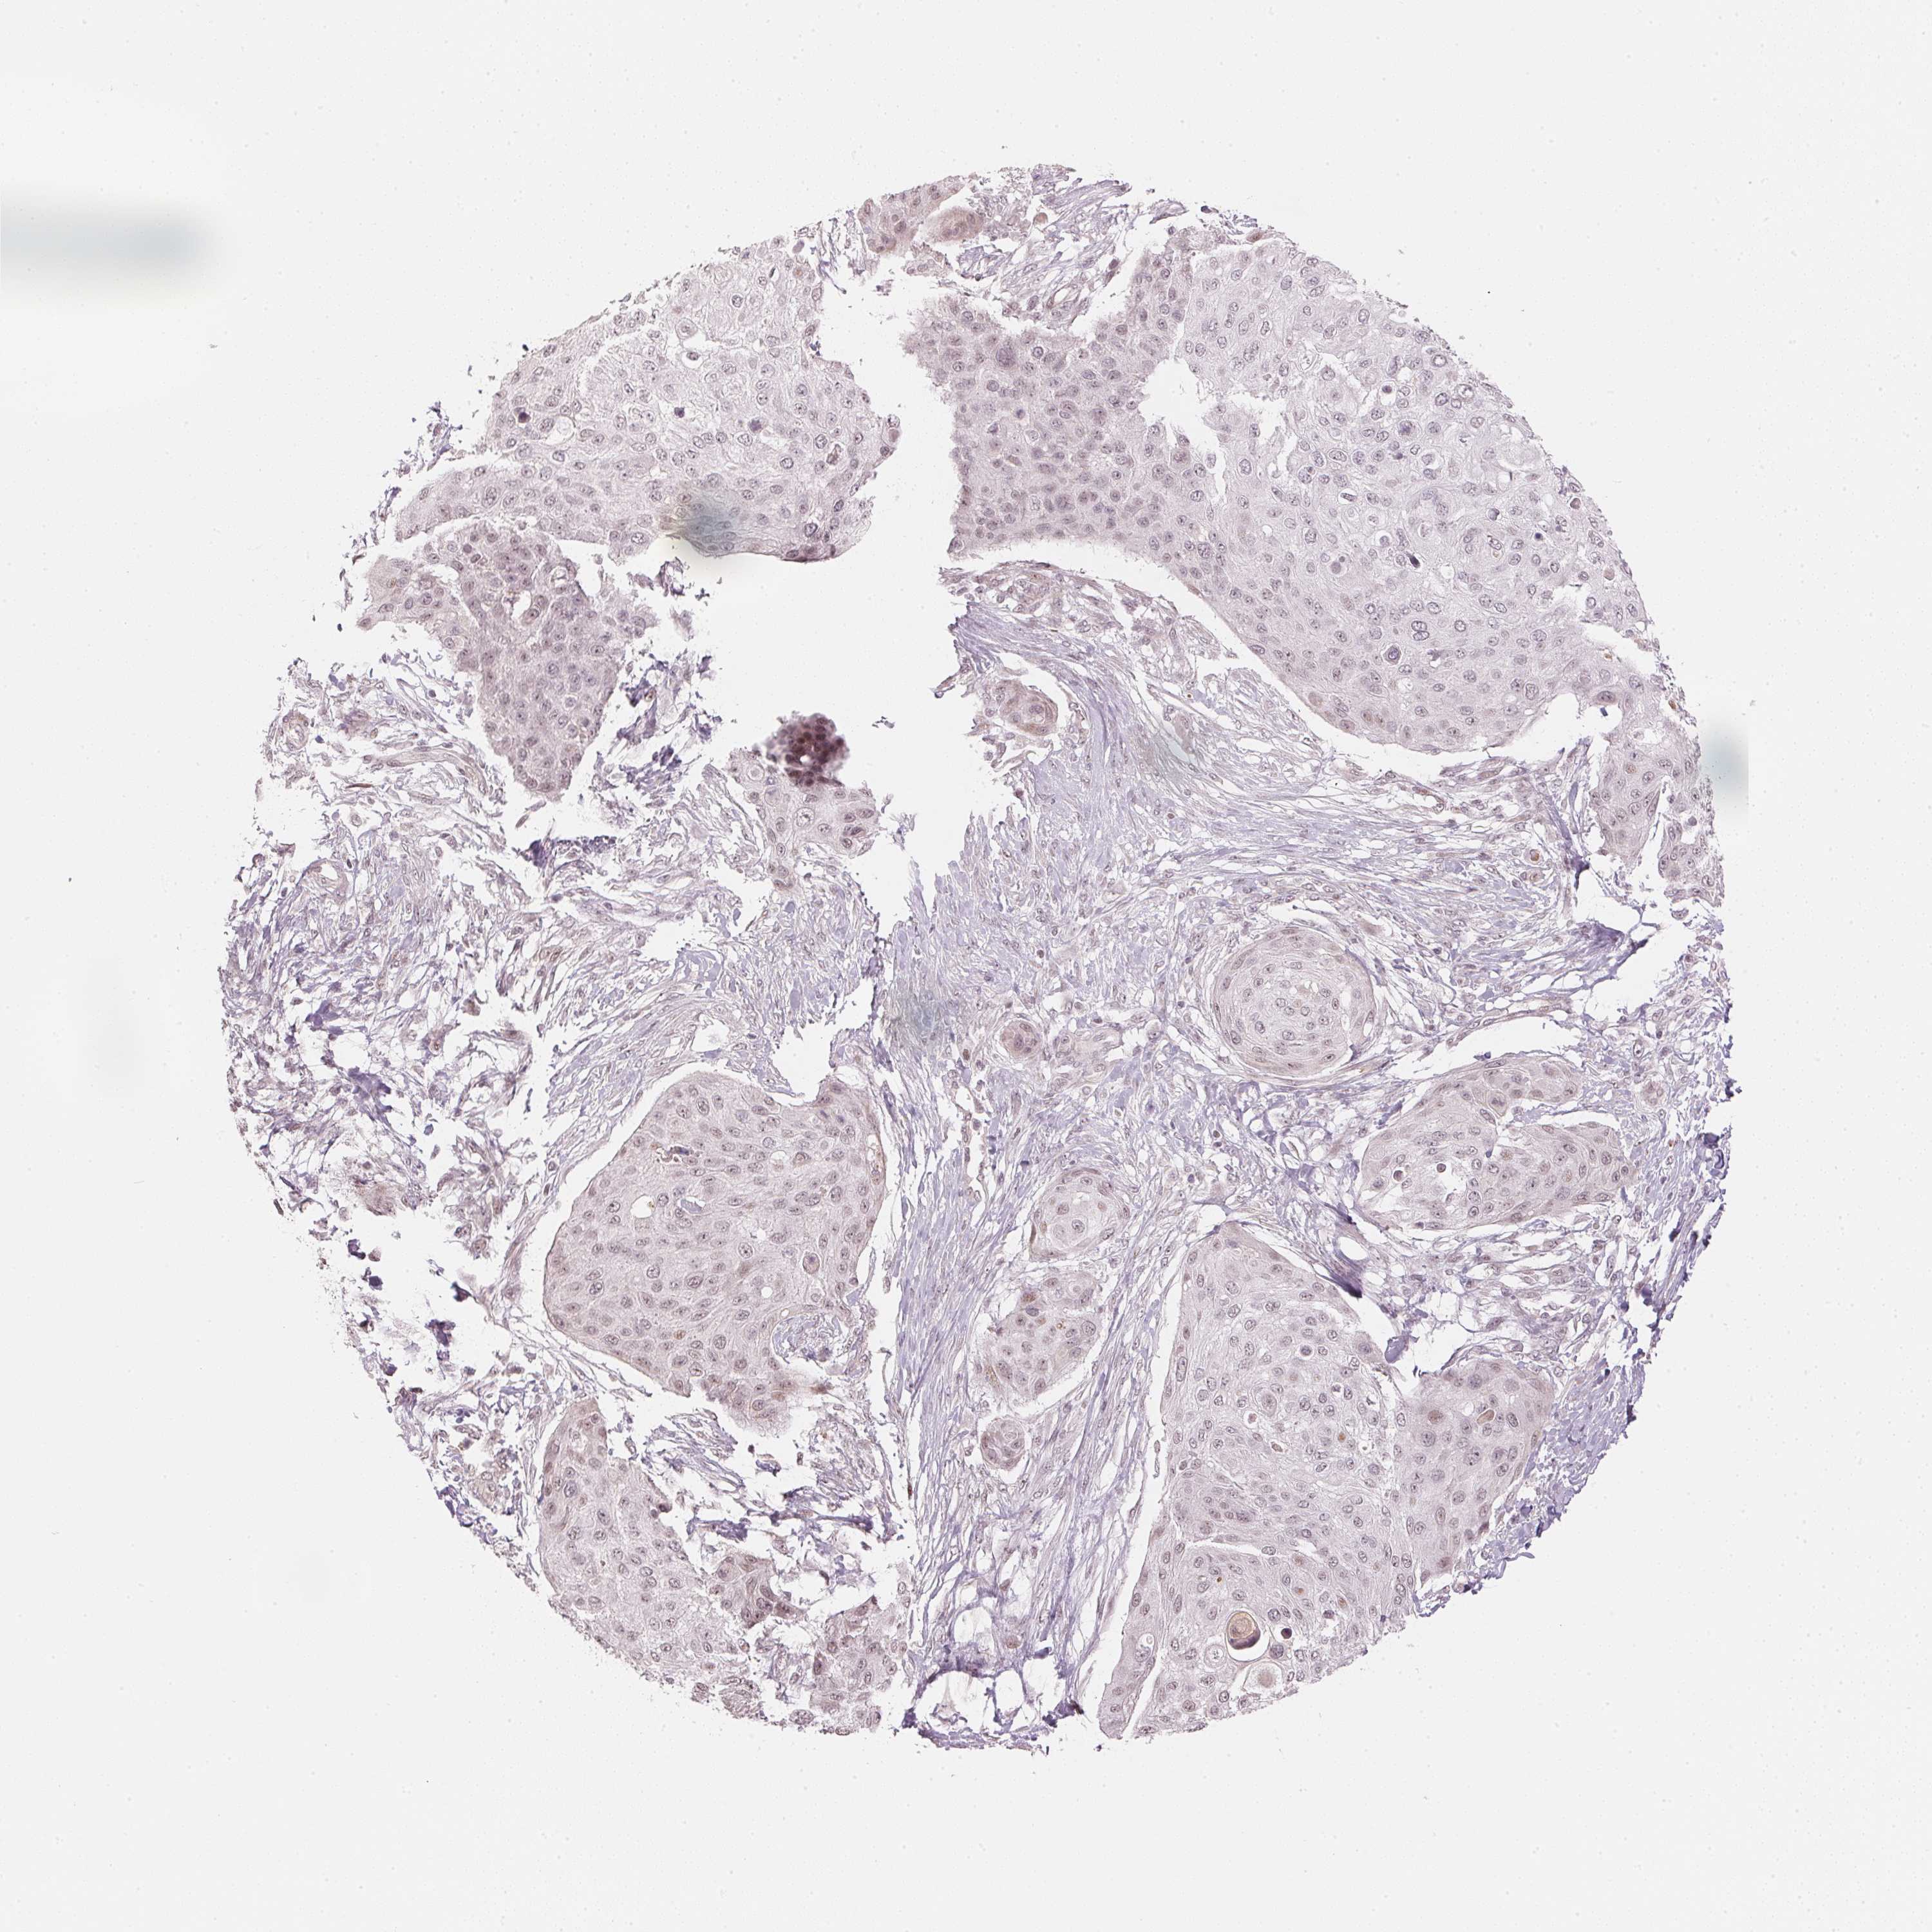

SKIN CANCER - Protein expressioni

A mouse-over function shows sample information and annotation data. Click on an image to view it in a full screen mode. Samples can be filtered based on level of antibody staining by selecting one or several of the following categories: high, medium, low and not detected. The assay and annotation is described here.

Antibody stainingi

Antibody staining in the annotated cell types in the current human tissue is reported as not detected, low, medium, or high, based on conventional immunohistochemistry profiling in selected tissues. This score is based on the combination of the staining intensity and fraction of stained cells.

Each image is clickable and will lead to virtual microscopy that enables deeper exploration of all samples and also displays staining intensity scores, fraction scores and subcellular localization as well as patient and tissue information for each sample.

Antibody HPA065052

Squamous cell carcinoma, NOS